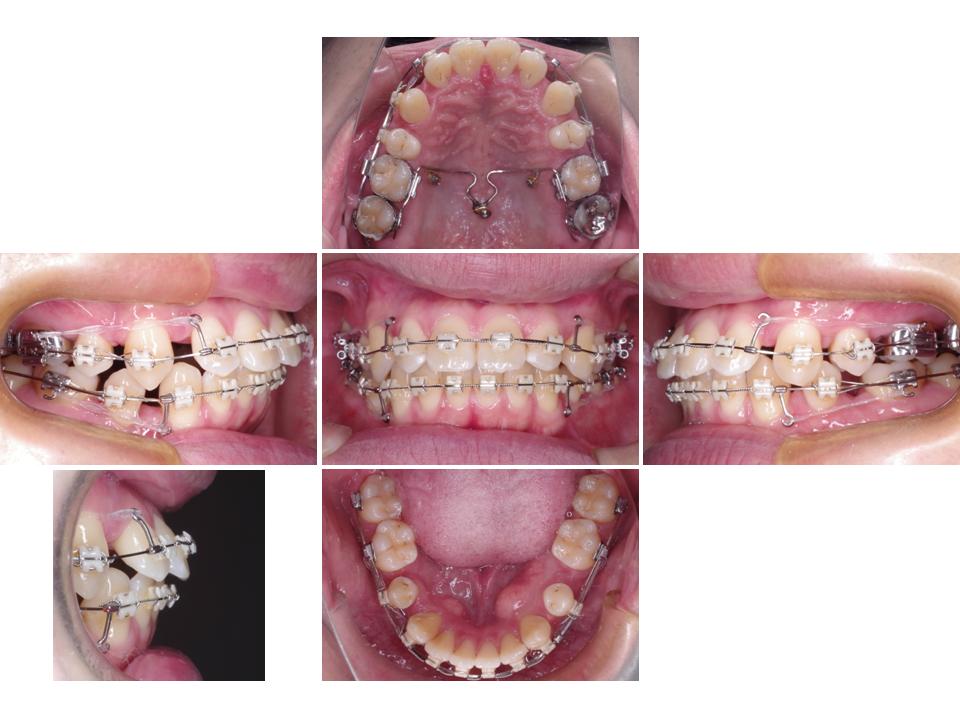

上下の歯の凸凹、出っ歯

かみ合わせが深く下の歯に装置が付けれなかったため、奥歯のかみ合わせを一時的に高くする処置を行い装置を装着しました。歯科矯正用アンカースクリューにより上の前歯を大きく後ろに下げながら下の歯の凸凹の改善を行うことができ、難しいかみ合わせにも関わらず一般的な矯正治療期間で治療を終えることができました。

| 主訴 | 上下の歯の凸凹、出っ歯 |

| 年齢・性別 | 22歳 / 女性 |

| 抜歯部位 | 上顎両側第一小臼歯、下顎両側第二小臼歯 |

| 装置 | メタルブラケット |

| 期間 | 2年6か月 |

治療前

治療中

治療後

治療費990,000円

通院回数32回